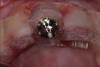

Fig 17. Piezosurgery was used for a minimally invasive extraction that did not damage the soft tissues.

Figure 17

Fig 18. Three-dimensional implant treatment planning software was used to ensure implant placement accuracy.

Figure 18

Fig 19. Surgical guide for implant placement.

Figure 19

Fig 20. The implant was placed immediately following extraction according to the treatment plan.

Figure 20